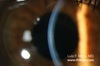

¿Qué signo se observa y de qué es indicativo?

Estría de Vogt, es indicativo de ectasia corneal